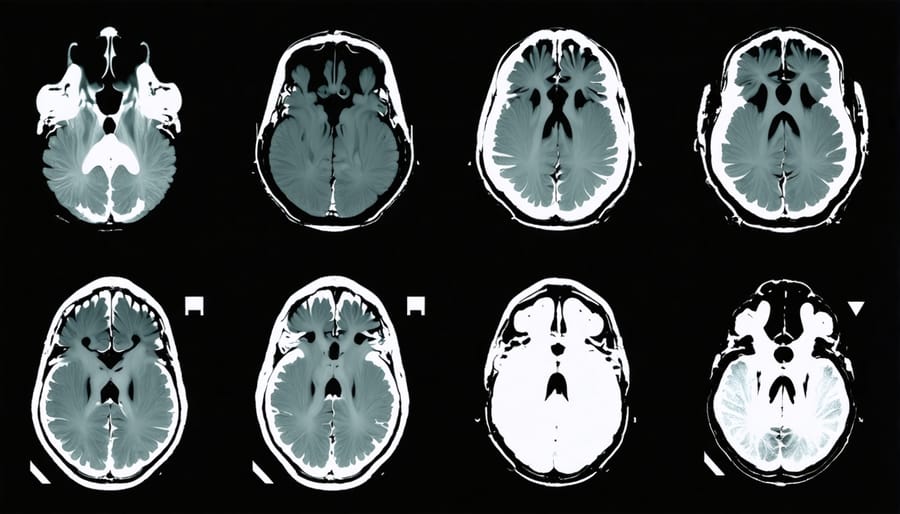

Structural MRI, meanwhile, doesn’t capture the brain in action like its functional cousin. Instead, it’s like taking high-resolution photographs of brain architecture. Researchers use these detailed anatomical maps to investigate whether long-term cannabis use might alter brain structure—questions about hippocampus size or changes in gray matter density. While these structural studies can’t tell us what’s happening moment-to-moment when someone uses THC, they offer crucial insights into potential lasting effects, helping scientists distinguish between temporary changes and more enduring transformations in the brain’s landscape.

When researchers use fMRI and PET scans to observe cannabis users, the hippocampus—your brain’s memory formation center—shows noticeably altered activity patterns. Think of the hippocampus as your brain’s filing clerk, constantly sorting and storing new information. Under THC’s influence, this clerk seems to take an extended coffee break. The imaging reveals decreased blood flow and reduced communication between the hippocampus and other memory-related regions.

This isn’t just abstract neuroscience—it explains that classic cannabis experience where you start telling a story and midway through, lose your train of thought entirely. One study showed participants a series of words while under THC’s effects. The brain scans revealed their hippocampus struggled to “light up” during the memory encoding process, like trying to save a document on a computer with a glitchy hard drive.

What’s particularly fascinating is that these effects appear temporary for most users. Once THC clears your system, the hippocampus generally returns to its normal bustling activity. However, chronic heavy use, especially when started during adolescence, shows more persistent changes in hippocampal structure and function—a finding that’s prompted serious conversations about the timing and frequency of cannabis use.

Picture your brain’s CEO—the prefrontal cortex—deciding to take an unexpected vacation. That’s essentially what neuroimaging studies reveal when Delta-9 THC enters the picture. This region, nestled right behind your forehead, normally acts as your brain’s executive manager, juggling decision-making, impulse control, and rational thinking. But when THC binds to cannabinoid receptors, brain scans show something fascinating: activity in this crucial control center dramatically decreases.

Functional MRI studies have captured this phenomenon beautifully, showing cooler colors—representing less activity—washing over the prefrontal regions. Meanwhile, other brain areas light up more intensely, particularly those involved in sensory processing and emotion. It’s not that your brain stops working; rather, it shifts priorities. The rational planner takes a backseat while the creative dreamer grabs the wheel, fundamentally altering how you process information and make decisions in those moments.

When researchers compare acute users (those experiencing their first or occasional exposures) with chronic users, they’re essentially watching two different movies. In acute users, THC lights up the brain like a fireworks display—the cerebellum buzzes with activity affecting coordination, the limbic system responds intensely to emotional stimuli, and the prefrontal cortex shows significant alterations in decision-making regions. It’s overwhelming because the brain hasn’t learned to compensate yet.

Chronic users tell a different story. Their scans often show what scientists call “blunted responses”—the same dose of THC produces less dramatic changes in blood flow and activity patterns. This isn’t necessarily good news; it’s evidence of tolerance. The brain has downregulated its cannabinoid receptors, similar to turning down the volume on speakers that have been blasting too long. Studies using PET scans have found that heavy, long-term users can have up to 20% fewer CB1 receptors in certain brain regions compared to non-users.

The more concerning findings involve structural changes. Some studies using MRI have reported reduced volume in the hippocampus and amygdala among chronic users—regions critical for memory and emotion. However, other research has failed to replicate these findings, and scientists debate whether observed changes represent actual tissue loss or temporary alterations in how brain cells hold water and nutrients.